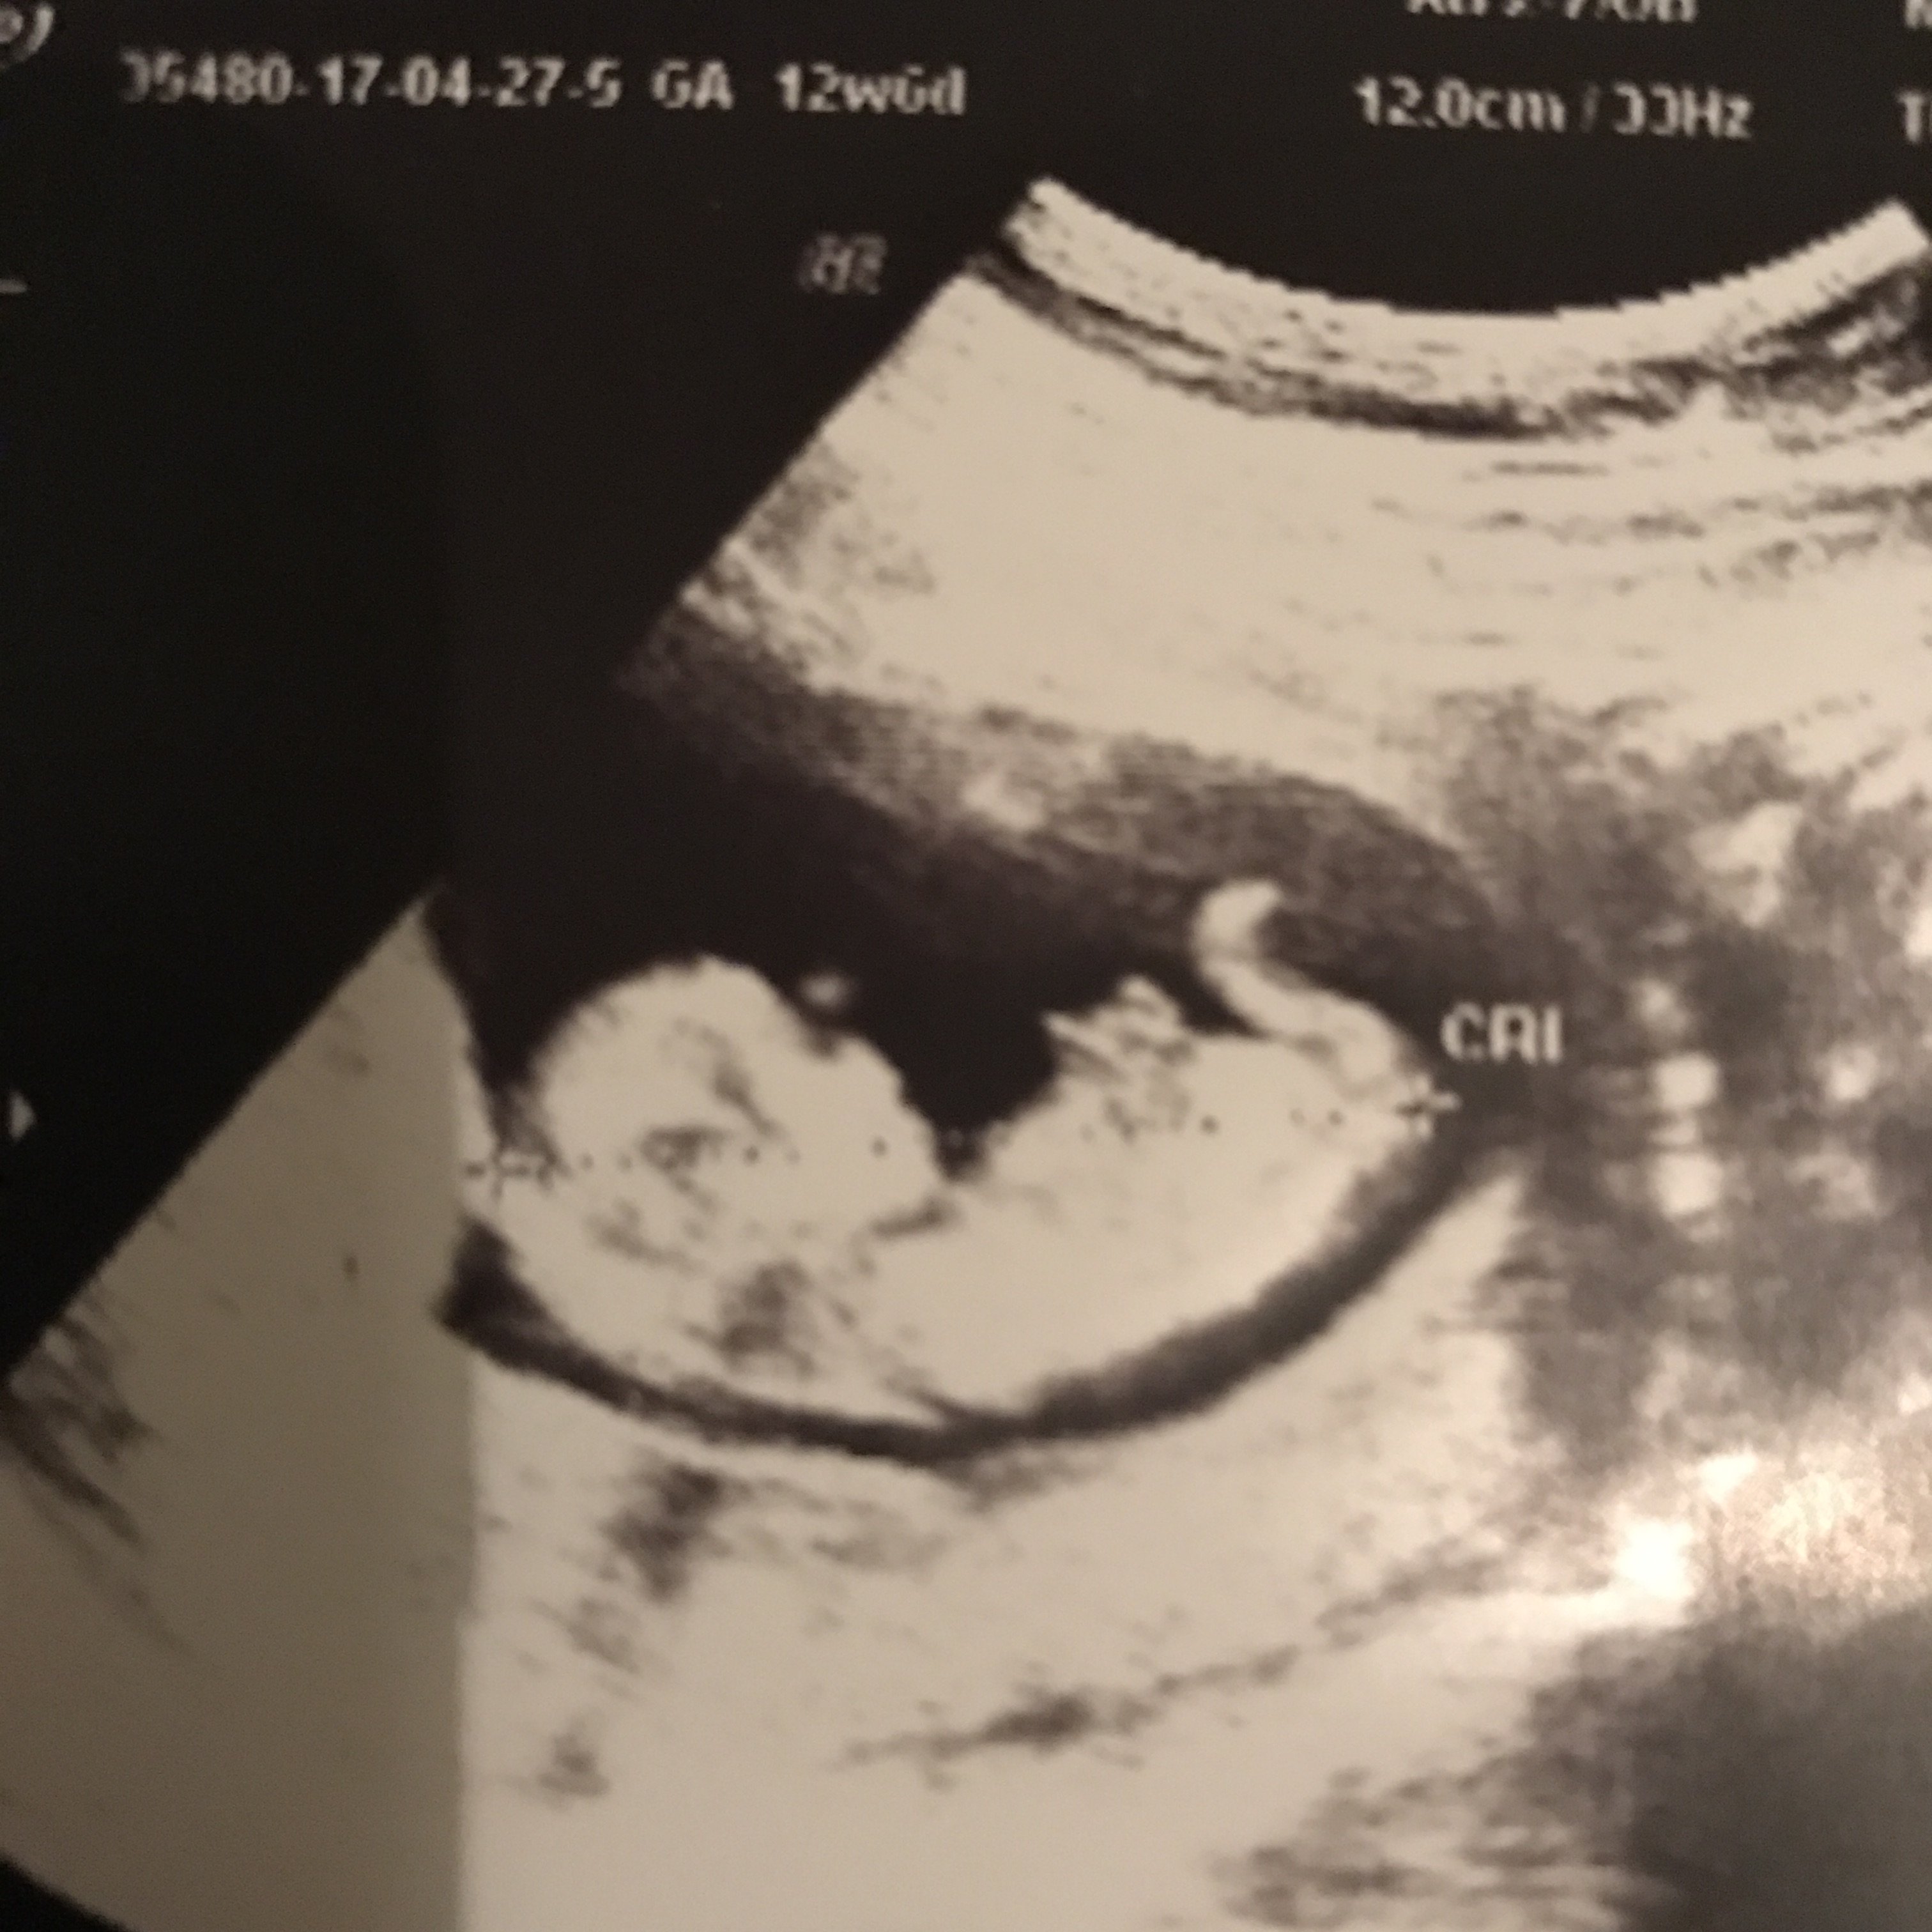

B Buglem2011 Yeni Üye Üye 26 Mayıs 2017 #285 Ekli dosyayı görüntüle 76905 Ekli dosyayı görüntüle 76906 sonunda yükledim banada yorum yaparmısınız tşkler şimdiden

Ekli dosyayı görüntüle 76905 Ekli dosyayı görüntüle 76906 sonunda yükledim banada yorum yaparmısınız tşkler şimdiden

HemşireniZ Aktif Üye Üye 26 Mayıs 2017 #287 Merhaba çıkıntının üzeri işaretli emin olmamakla birlikte bebeğinizin cinsiyetini kız olarak düşünüyorum.

Merhaba çıkıntının üzeri işaretli emin olmamakla birlikte bebeğinizin cinsiyetini kız olarak düşünüyorum.